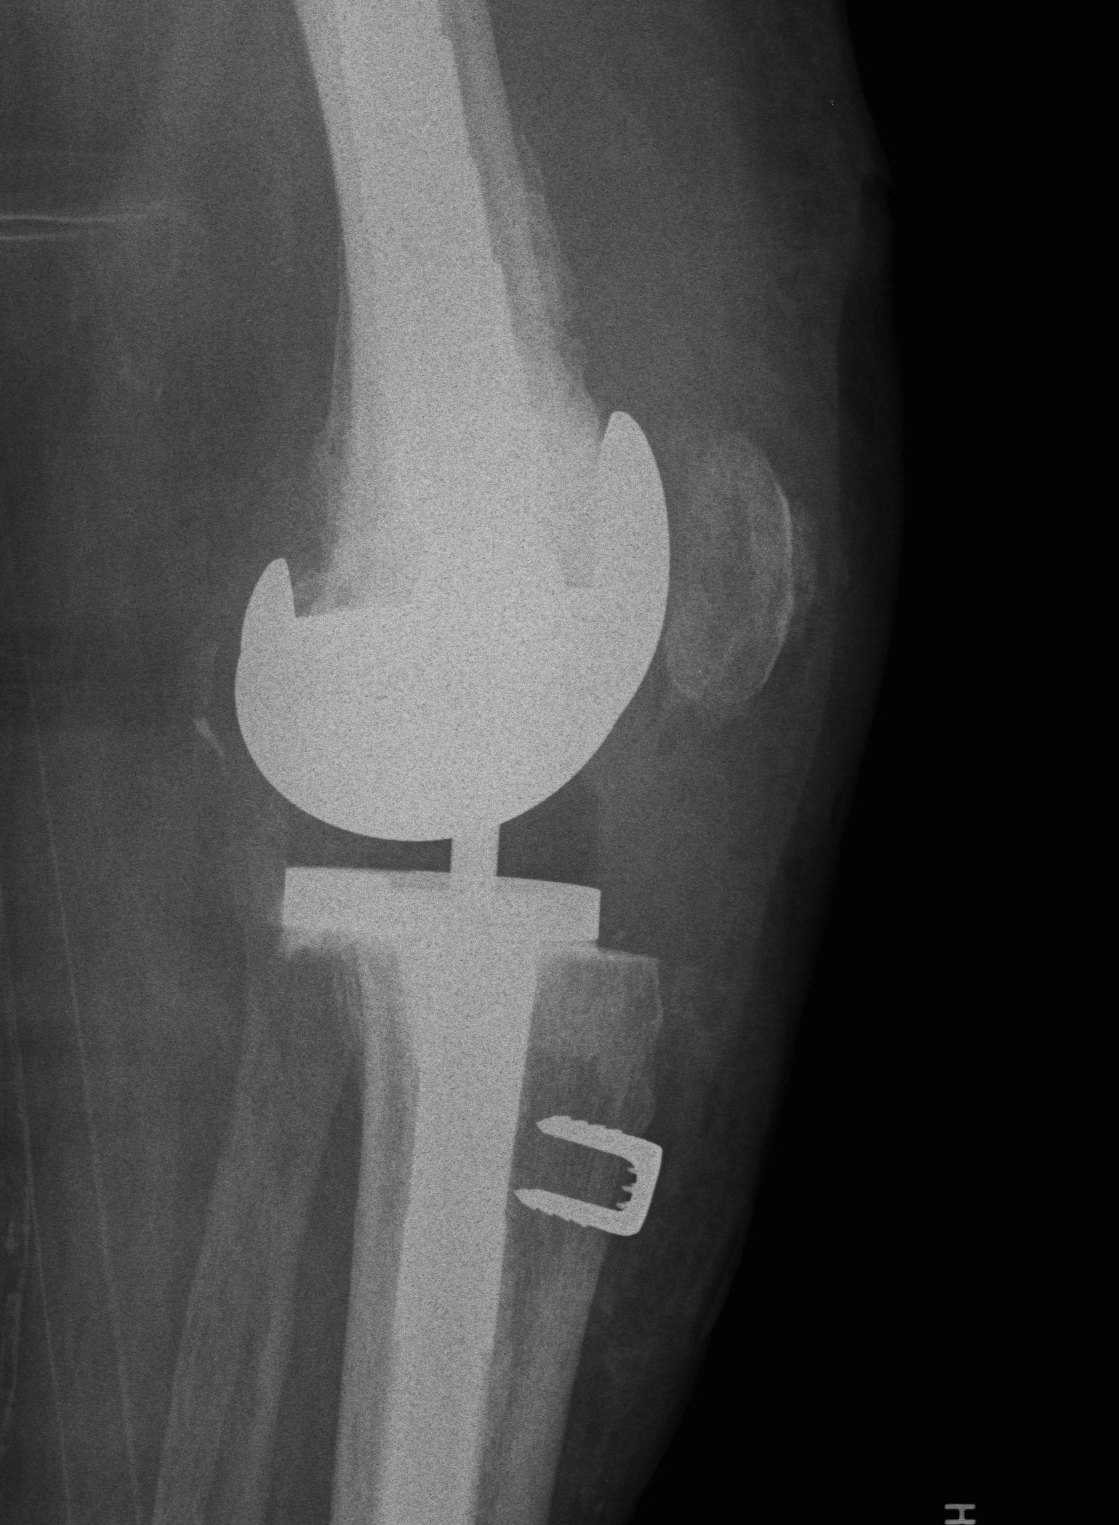

3. Tibial tuberosity osteotomy

- 6-10 cm long, 2 cm wide, 1 cm thick

- lateral periosteum intact / lever open laterally

- bypass osteotomy with stem

- need to wire back around the tibial stem

- place wires before definitive stem

- drill holes medially and laterally

- can use diverging screws as well